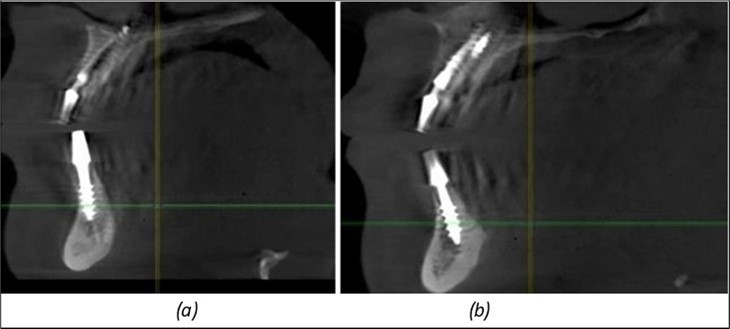

Figure 9.Implants in the pterygoid plateau area: (a) TPG implant fixed in the maxillary-sphenoid junction area, quadrant 1; (b) TPG implant fixed in the maxillary-sphenoid junction area, quadrant 2.

Figure 10.Implants in the palatal sinus cortical area to avoid bone grafting: (a) BCS implant partially fixed in the graft material mass, partially in the palatal cortex; (b) Implant fixed in the palatal cortex at the junction with the nasal cortex, behind the graft material mass.